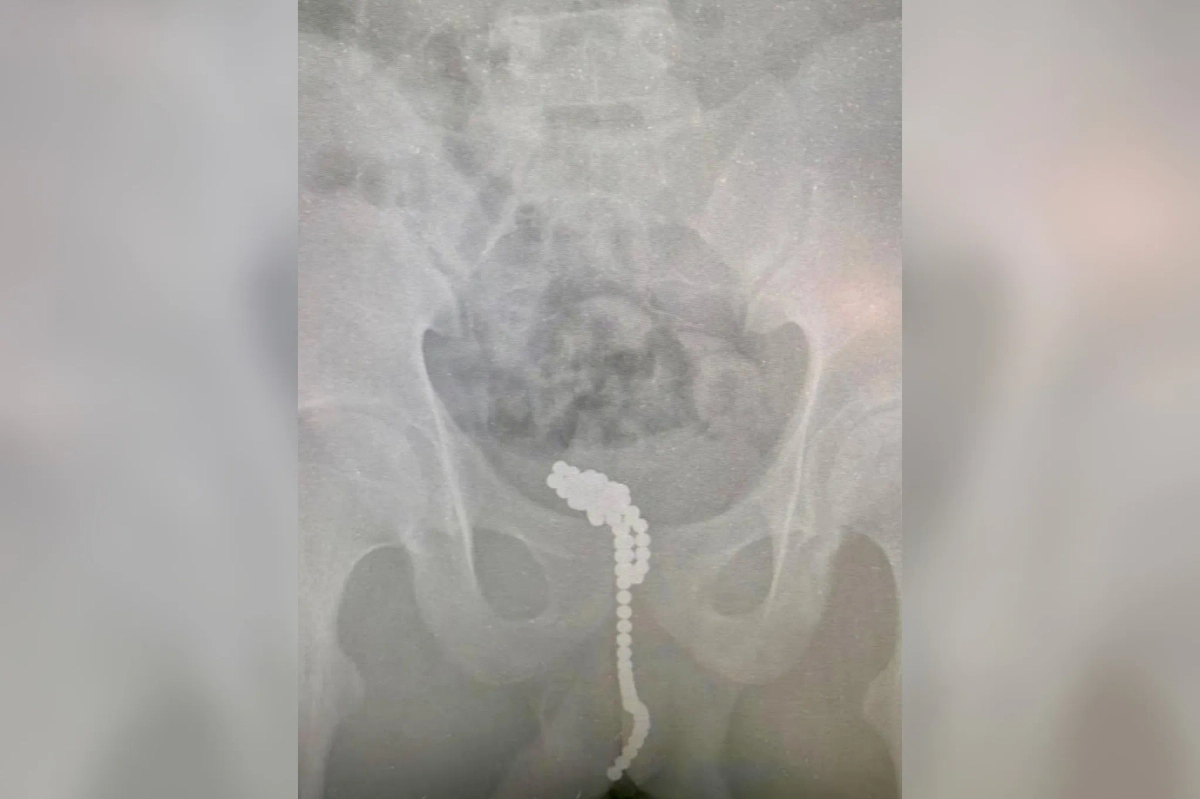

Магниты, которые достали из мочевого пузыря и уретры подростка. Обложка © Предоставлено Life.ru

Рентген ребёнка до хирургического вмешательства. Фото © Предоставлено Life.ru

Юный пациент обратился в приёмный покой Московского областного центра охраны материнства и детства (МОЦОМД) с острой задержкой мочи, что угрожало разрывом мочевого пузыря. В ходе обследования медики обнаружили в организме парня несколько десятков магнитных шариков. Инородные тела пришлось удалять через небольшой разрез в мочевом пузыре. Контрольный рентген подтвердил, что никаких магнитов в мальчике не осталось.